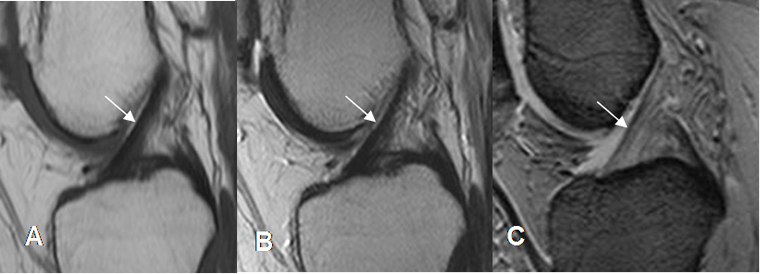

Para una adecuada valoración del LCA, se deben orientar los cortes sagitales con una rotación externa entre 20º y 25º de la rodilla.

El ligamento se aprecia como una estructura hipointensa en todas las secuencias, pudiendo reconocer sus 2 bandas. Pueden encontrarse áreas hiperintensas en su parte distal, por interposición de grasa o sinovial entre las fibras o degeneración mucoide. (2). (Fig 13 y 14).

La orientación del LCA es uno de los signos con mayor sensibilidad y especificidad, de lesión ligamentaria.

Fig 13. LCA normal.

A: RM sagital en T1, B: RM sagital en T2 y C: RM sagital en FFE. Ligamento normal,

hipointenso en todas las secuencias.